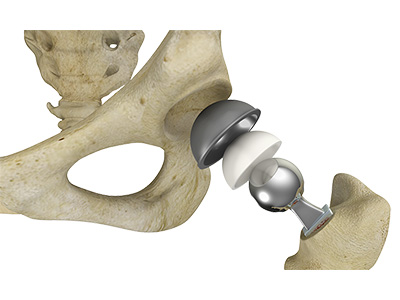

The hip joint is the junction where the hip joins the leg to the trunk of the body. It is comprised of two bones: the thigh bone or femur and the pelvis which is made up of three bones called ilium, ischium, and pubis. The ball of the hip joint is made by the femoral head while the socket is formed by the acetabulum. The Acetabulum is a deep, circular socket formed on the outer edge of the pelvis by the union of three bones: ilium, ischium, and pubis. The lower part of the ilium is attached by the pubis while the ischium is considerably behind the pubis. The stability of the hip is provided by the joint capsule or acetabulum and the muscles and ligaments which surround and support the hip joint.

The head of the femur rotates and glides within the acetabulum. A fibrocartilagenous lining called the labrum is attached to the acetabulum and further increases the depth of the socket.

The femur or thigh bone is one of the longest bones in the human body. The upper part of the thigh bone consists of the femoral head, femoral neck, and greater and lesser trochanters. The head of the femur joins the pelvis (acetabulum) to form the hip joint. Next, to the femoral neck, there are two protrusions known as greater and lesser trochanters which serve as sites of muscle attachment.

Articular cartilage is the thin, tough, flexible, and slippery surface lubricated by synovial fluid that covers the weight-bearing bones of the body. It enables smooth movements of the bones and reduces friction.

Robotic Assisted Hip Replacement Total Hip Replacement

Total Hip Replacement Outpatient Hip Replacement